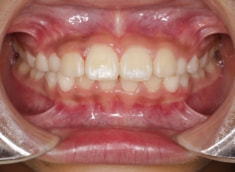

小児期ケース:叢生(ガタガタ)

治療法:拡大プレート+フルパッシブブラケット(クリアスナップ)

治療後(1年1ヶ月後)